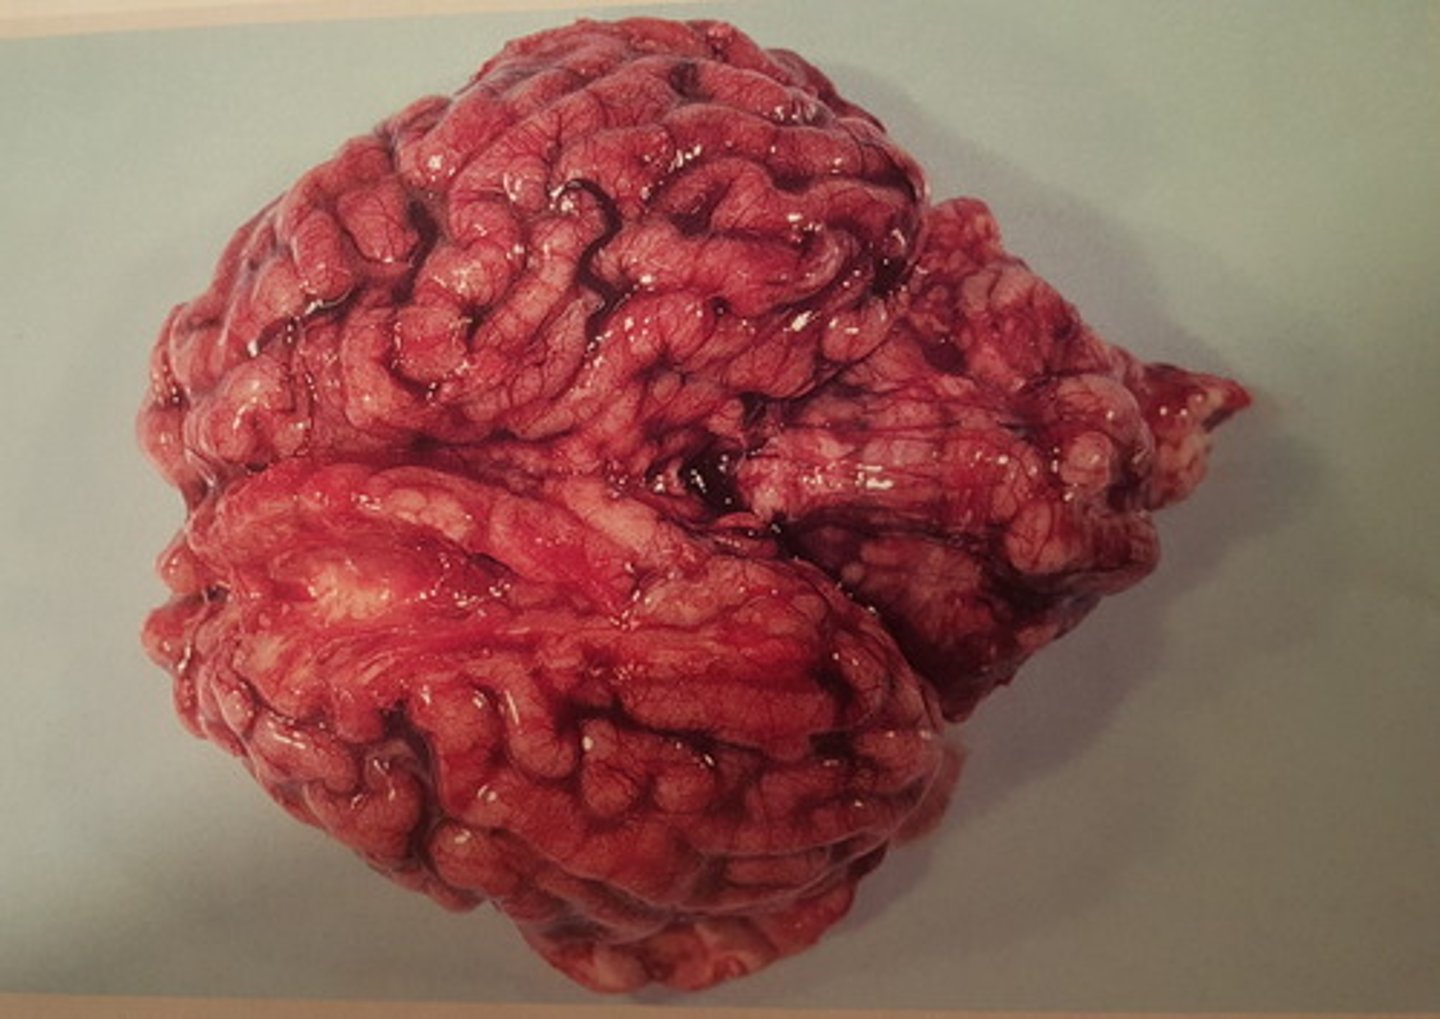

kronisk diffus pyocephali med dilation af ventrikelsystemet

Hjerne fra okse. Patoanatomisk diagnose?

kronisk dissemineret apostematøs encephalitis med abscesdannelse

Hjerne fra okse. Patoanatomisk diagnose?

kronisk dissemineret apostematøs encephalitis. Kan opstå som led i pyæmi

Hjerne fra okse. Patoanatomisk diagnose? Hvordan kan det opstå?